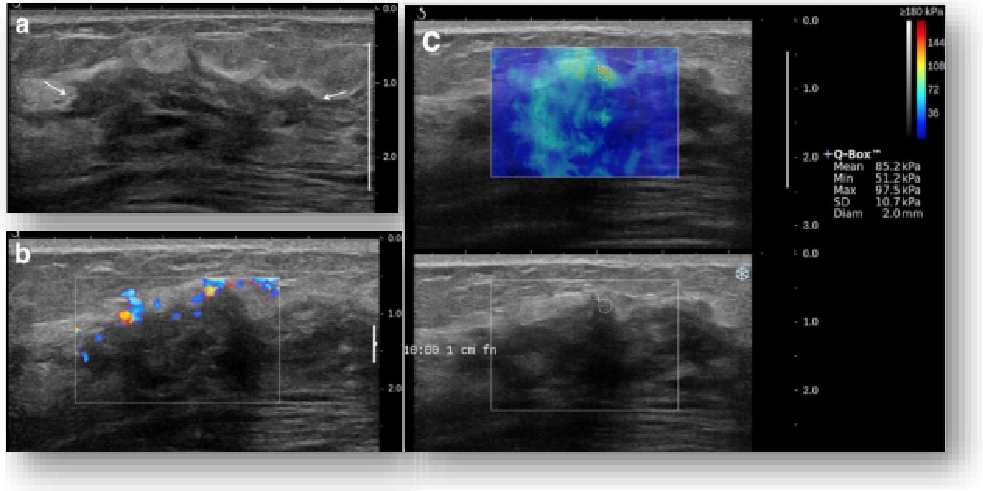

平面波超微细血流显像

能够提供更多真实的组织细小及末梢血管的血流信息,直观的观察组织内部的血管架构及血流形态的情况,提供临床更多有价值的诊断信息。

临床应用:

肿瘤鉴别诊断(肝脏、肾脏、甲状腺、乳腺、  涎腺等)

淋巴结评价(炎症、肿瘤)

肌骨系统临床诊断和疗效监测(关节、滑膜、韧带、肌肉炎症、 损伤等)

斑块内新生血管评估

超声介入术前进针方案提供血流参考信息

超声介入术后疗效评估

实时剪切波弹性成像

评估组织的软硬,并且提供定量数值,从而提示组织的良恶性。

鉴别诊断、精准分级、定量评价、穿刺引导、疗效评估、随访观察

image.png

恶性占位常常向周边组织进行侵润及扩散,二维很难观察到浸润部分的边界。使用实时剪切波成像能够对占位及周边组织进行硬度评估,通过颜色编码来区分不同组织的硬度信息,直观的观察占位组织的边界信息,更方便区分占位组织和正常组织的边界,准确评估消融范围。